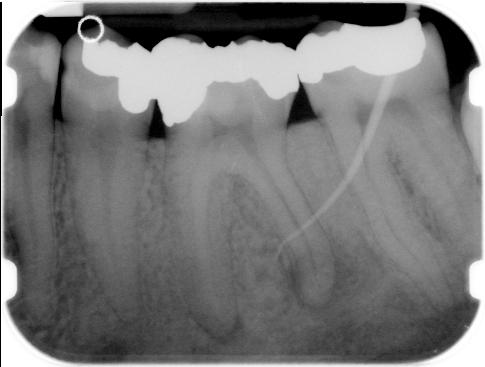

De oorsprong van de fistel wordt opgezocht door een guttaperchastift zover mogelijk in het fistelkanaal te steken en vervolgens een X-foto te nemen. De uitvoergang zit niet standaard precies ter plaatse van het periapicale proces.